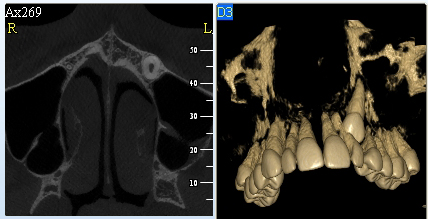

Pomocí tohoto přístroje je možné zjisti skutečnou situaci v čelistních kostech pacienta tedy množství kosti - můžeme změřit skutečnou šířku i výšku kosti, i kvalitu kosti (hustotu) v místě uvažované implantace. 3D (tříprostorové) zobrazení umožňuje

zvýšit prostorovou představu operatéra ještě před vlastní operací a zároveň pacientovi lépe objasnit a ukázat oblast plánovaného zavedení implantátu.

Pacient „neumí číst“ RTG snímky, ale díky 3D zobrazení vidí „svoji skutečnou čelist“ – např. jak je nízká či úzká, vidí průběh nervu nebo velikost čelistní dutiny, což mu umožní i pochopení nutnosti v některých případech provést pomocné zákroky

ještě před vlastním zavedením implantátu (více - Augmentace - kostní štěp, sinus lift, kostní granulát...).